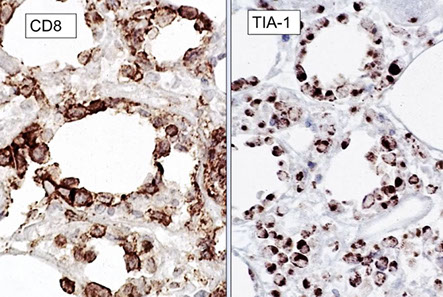

Cutaneous lymphoid hyperplasia in a 72-year-old man who presented with several purple-brown plaques on his cheeks and temples. A, The nodular infiltrate extends through the dermis with sparring of the overlying epidermis. B, It is characterized by scattered follicles with well-defined, reactive-appearing germinal centers, some of which have surrounding mantle zones. Many CD20-positive B cells are in the reactive follicles (C), and more numerous CD3-positive small T cells are present in the interfollicular areas (D). B-cell clonality studies (not shown) were negative for a clonal IGH or IGK gene rearrangement. [19]